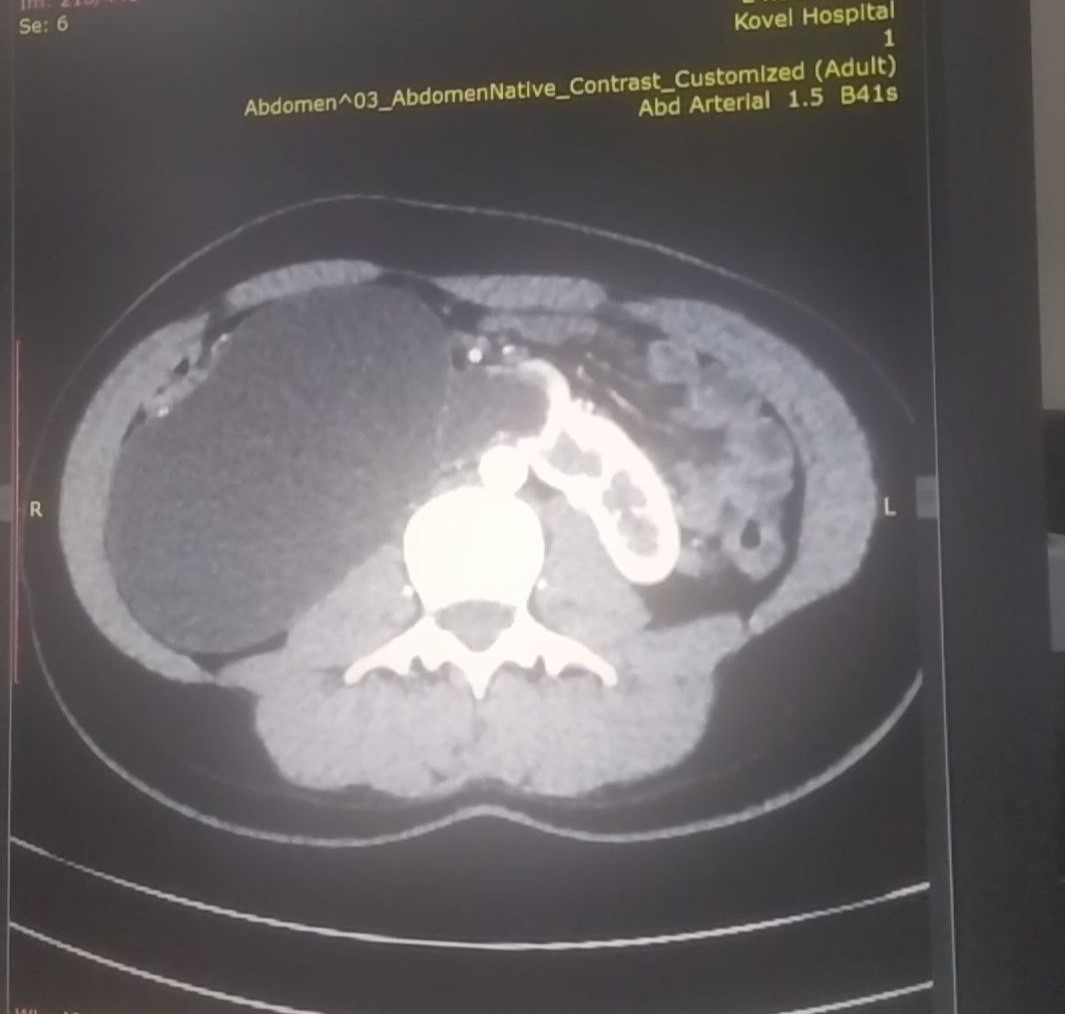

17-річна пацієнтка мала вроджену ваду сечовидільної системи - підковоподібну нирку (зрощення двох нирок). Стан її здоров’я погіршувався упродовж багатьох років, аж поки права половина підковоподібної нирки перестала функціонувати.

Хвору доставили в лікарню у важкому стані з вираженим больовим синдромом та наявністю гіпертонічного кризу. Через звуження у сечоводі та ускладнення відтоку сечі, об’єм рідини в нирці сягнув критичного рівня. А збільшення її розмірів стало помітним навіть зовні.

Лікарі діагностували термінальний гідронефроз із наслідками, гідронефротичну трансформацію правої половини підковоподібної нирки, вторинну артеріальну гіпертензію.